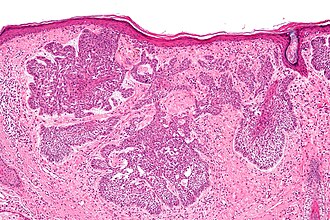

Basal cell carcinoma, a component of NBCCS. H&E stain.

- Basal cell carcinoma - on average have their first tumour in their 20s.[3]